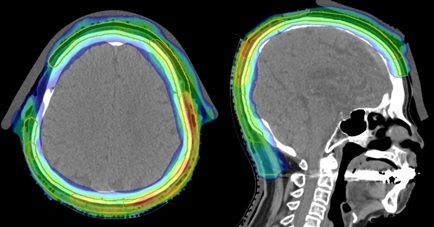

頭皮にできた血管肉腫。頭皮に沿って進展しやすく頭皮の大部分に照射が必要。

IMRTを用いて頭蓋内(脳)が照射されるのを最小限に抑えている。